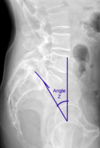

Slip angle greater than what degree is associated with greater risk of progression?

>50 degrees